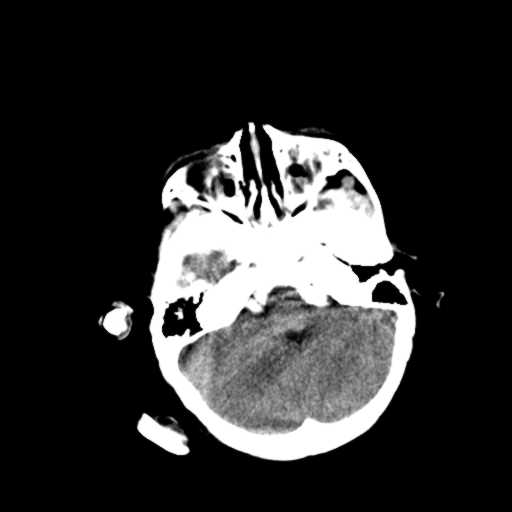

m,3y,外伤一天,无明显其它症状.

有点迷糊了:楼主兄弟要我们做什么?图片没有发全,该继续扫描的没有继续往下扫,不明白。能看的清楚是:

1.双侧上颌窦、筛窦炎。

2.左侧上颌窦后壁部分骨质缺损,内有一牙齿样高密度,周围似乎无明显囊肿形成(没有继续往下扫描,而且只有骨窗,不便观察)。暂考虑左侧上颌窦牙源性囊肿可能。

3.小脑以及右侧颞叶无明显异常,颅盖以及颅底诸骨未见明显骨折,双侧枕骨内板蛛网膜粒压迹多、略深。

1.右小脑半球外侧影为手指产生的伪影?硬膜外血肿?